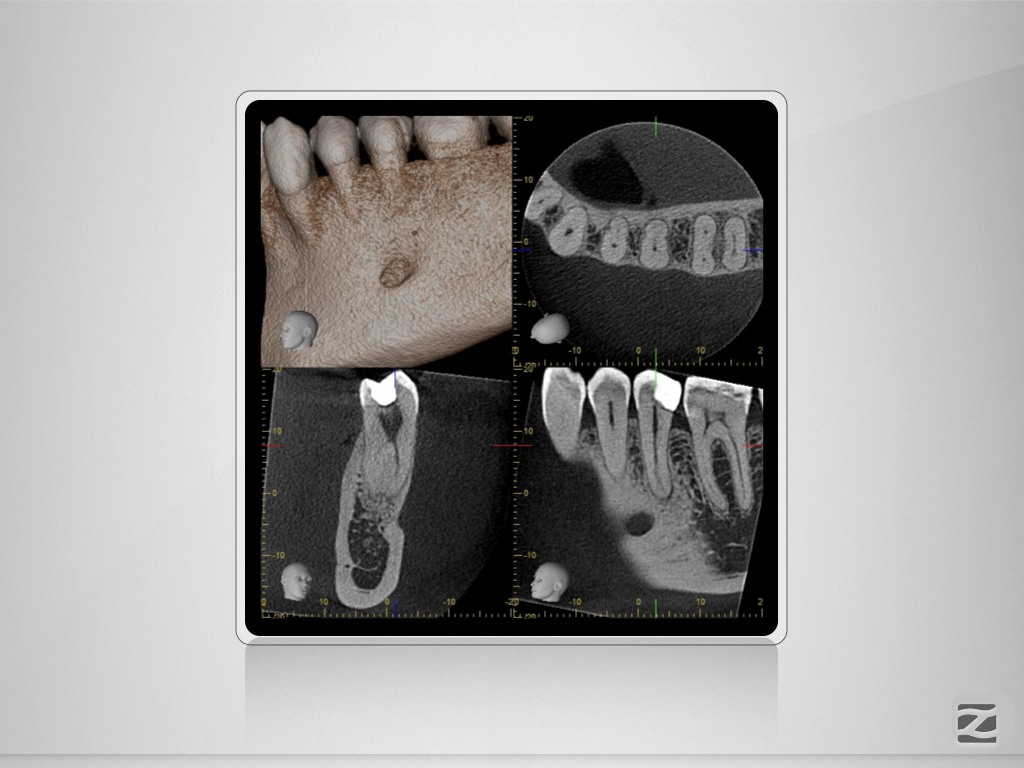

35D.003

35 mit tiefer Aufgabelung